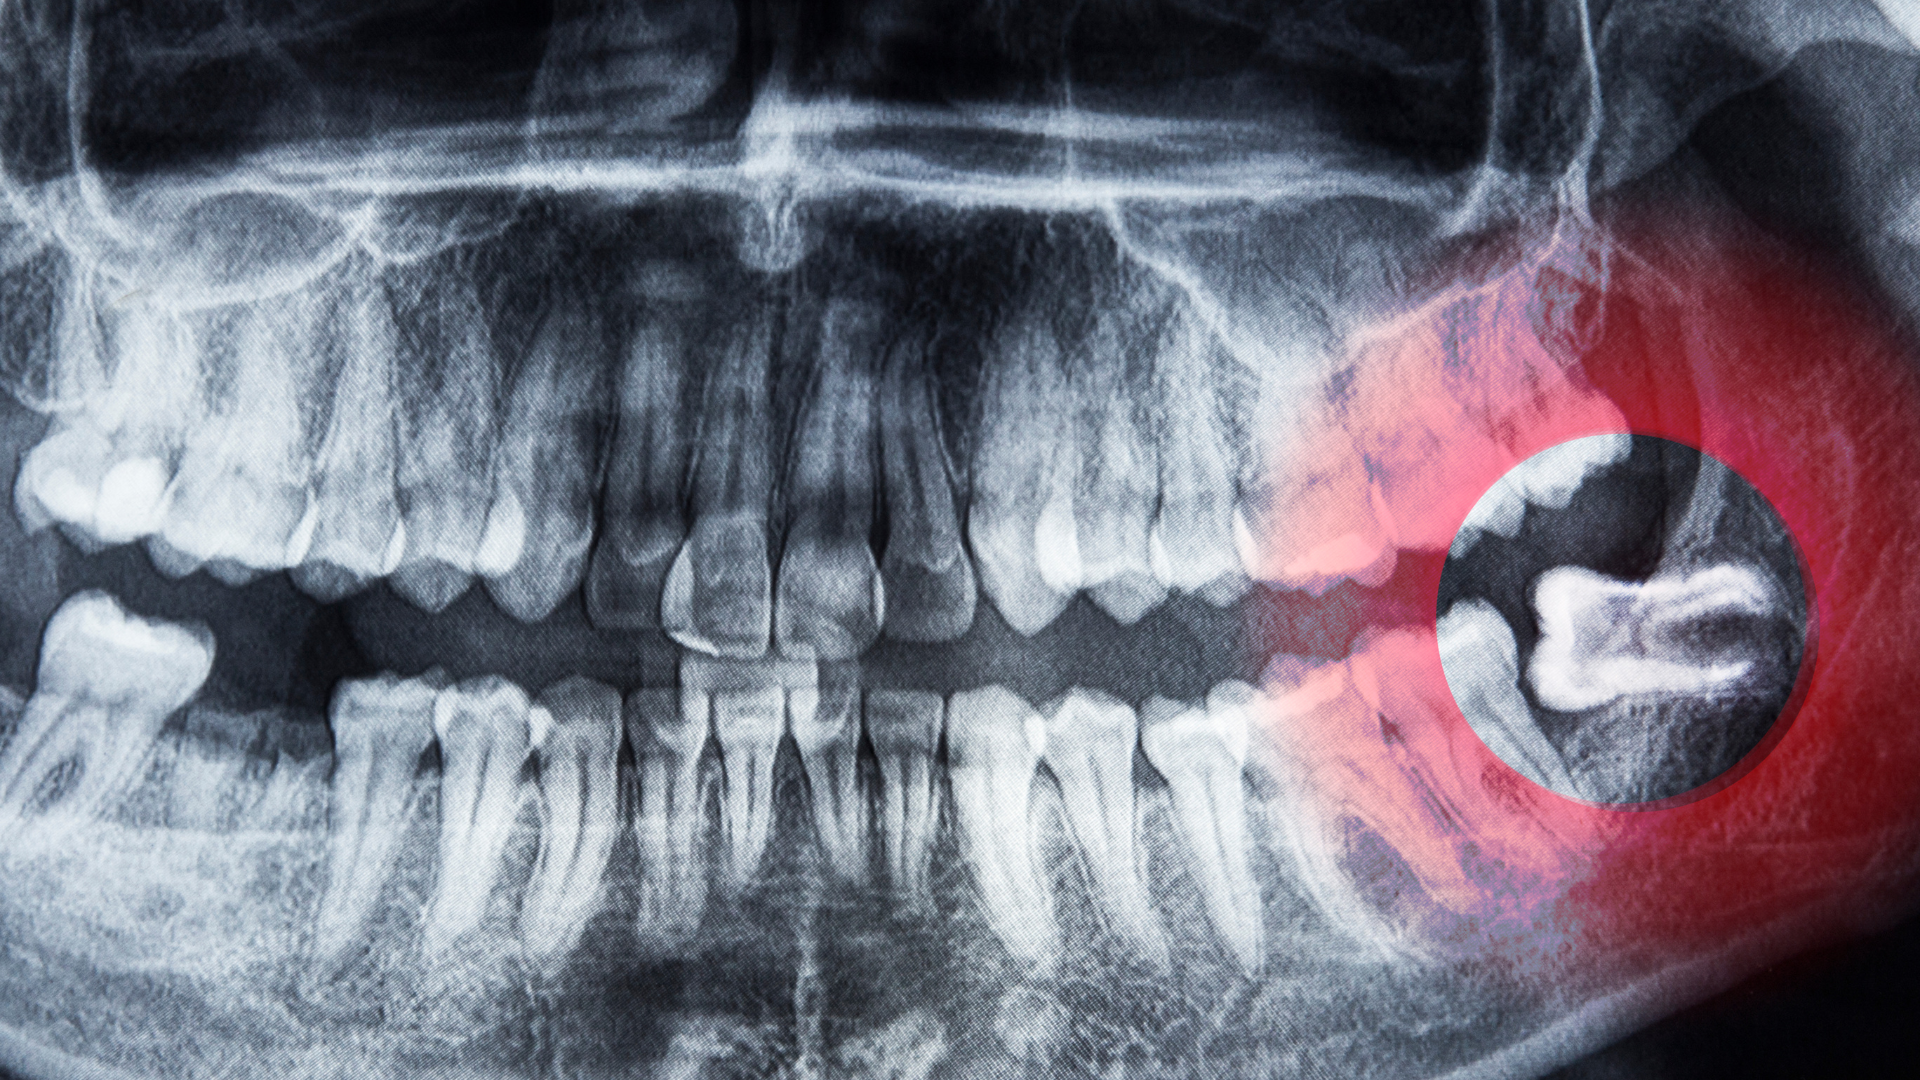

Răng khôn mọc lệch ngang là tình trạng thân răng nằm ngang, đâm vào răng số 7 hoặc xương hàm. Điều này khiến răng bị kẹt hoàn toàn hoặc một phần dưới nướu.

Các bất thường này khiến răng khôn không thể mọc thẳng nên nằm ngang và gây đau hoặc chèn ép sang răng bên cạnh.

- Chụp X quang hoặc CT để xác định hướng mọc và liên quan với dây thần kinh.